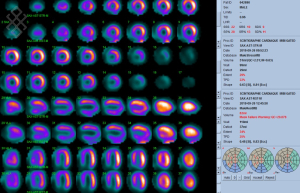

Scintigraphie Cardiaque

La phase de stress se déroulera en 4 étapes. Premièrement, il y aura la pose d'une voie veineuse. Deuxièmement, un test d'effort pharmacologique ou par pédalage sera réalisé. Troisièmement, il y aura une pause de 30 minutes. Quatrièrement, l'acquisition des images sera effectuée.